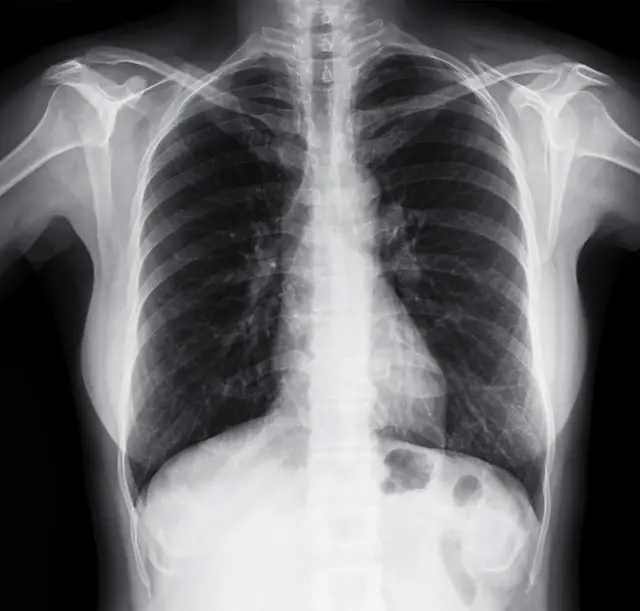

رادیو گرافی یا پرتونگاری

در این شیوه اشعه ایکس به بخش مورد نظر بدن بیمار تابانده شده و تصویر آن بر روی صفحات مخصوص ثبت میشود. این روش به علت دسترسی وسیع، سرعت و هزینه نسبتا پایین آن همچنان مرسومترین و پرکاربردترین روش تصویربرداری است.

از آنجایی که بدن انسان از مواد مختلف با تراکم متفاوت ساخته شده است، اشعه ایکس با گذر از لایههای کم تراکم بدن و توقف در لایههایی متراکم تصاویری را پدید میآورد که به تشخیص بیماریها کمک میکند؛ به عنوان مثال شکستگی استخوان، پوسیدگی دندان و عفونت ریه از جمله بیماریهایی هستند که برای تشخیص آنها از رادیوگرافی استفاده میشود.